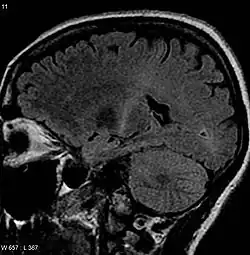

Because symptoms of ALS can be similar to those of a wide variety of other, more treatable diseases or disorders, appropriate tests must be conducted to exclude the possibility of other conditions. One of these tests is electromyography (EMG), a special recording technique that detects electrical activity in muscles. Certain EMG findings can support the diagnosis of ALS. Another common test measures nerve conduction velocity (NCV).[92] Specific abnormalities in the NCV results may suggest, for example, that the person has a form of peripheral neuropathy (damage to peripheral nerves) or myopathy (muscle disease) rather than ALS. While a magnetic resonance imaging (MRI) is often normal in people with early-stage ALS, it can reveal evidence of other problems that may be causing the symptoms, such as a spinal cord tumor, multiple sclerosis, a herniated disc in the neck, syringomyelia, or cervical spondylosis.[3]